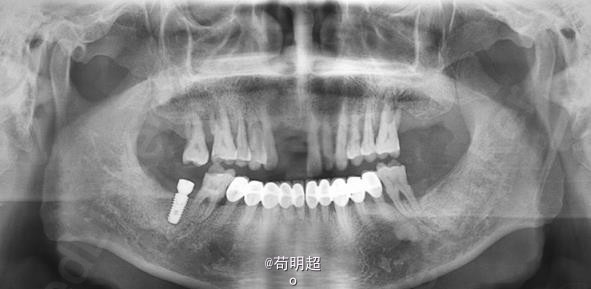

47牙齿种植修复

患者,男,40岁,47牙缺失要求种植。平素体质一般,无药物、食物过敏史,无高血压、心脏病等系统病史。